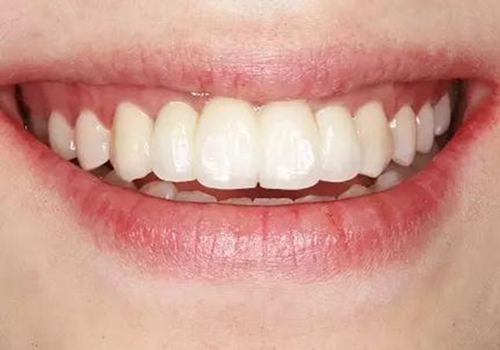

圖37 戴入全瓷修復(fù)體局部舌側(cè)觀 圖38 永久修復(fù)后微笑

圖39 永久修復(fù)后大笑

3、通過制作個(gè)性化轉(zhuǎn)移桿,將種植體周圍軟組織的形態(tài)輪廓精確地復(fù)制并轉(zhuǎn)移到模型上,個(gè)性化制作的氧化鋯基臺(tái)及全瓷修復(fù)體,生物相容性及美學(xué)效果良好,患者對(duì)最終修復(fù)效果滿意。